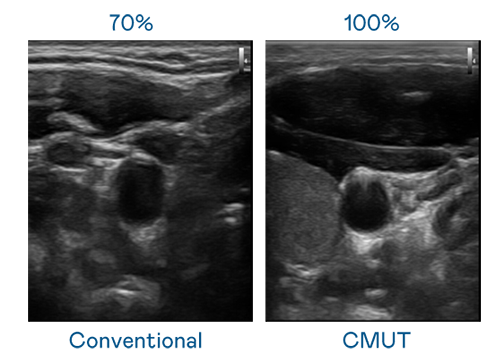

CMUT 技术是一种用电容式微机电元件来产生超音波讯号的技术。与传统 PZT 压电式技术相比,CMUT 频宽增加 30%,更宽频的超音波讯号让影像解析度大幅提升,是实现高影像品质医疗超音波扫描、促进精准医疗发展的关键技术。

大频宽带来超清晰影像

超音波影像的解析度高低,首先取决于探头能发出的讯号频宽。友达 CMUT 可提供高清晰的超音波讯号,提供高频宽、高灵敏度、影像纹理细节更高的超音波影像,协助医护人员缩短影像判读时间及利用精准的医疗影像进行诊断。